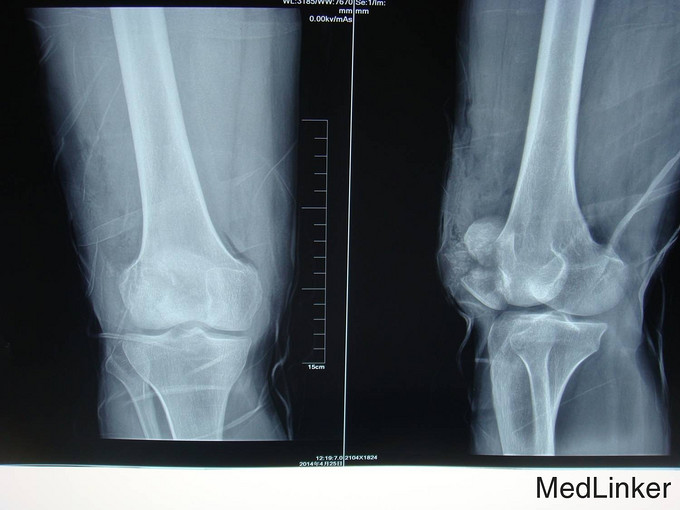

患者自述于2014年4月24日11点左右自马车坠落,摔伤致左膝关节疼痛、流血、活动受限,患者于当地医院行左膝X线检查,提示:左髌骨骨折,包扎,为进一步处理。患者现无意识障碍,无视物不清,无头晕、头痛,无恶心、呕吐,无胸闷及呼吸困难,无腹胀、腹痛。现平素饮食睡眠良好,二便如常。发病近期体重无明显下降。

左膝见一长约10cm的开放口,压痛(+)。未触及骨擦感及异常活动,未闻及骨擦音,患肢无明显 麻木,左下肢血运良好,余肢体查体未见明显异常。